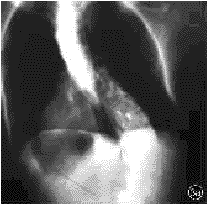

本组特发性脊柱侧凸患者占总病例数的74.7%(464/621),与文献报道的75%~80%相一致。但如果单独分析9~28岁常见手术年龄组的脊柱侧凸病例,则发现非特发性脊柱侧凸的构成百分比明显上升,由总病例数的25.3%(157/621)上升至34.0%(133/391)。表明在9~28岁这一常见手术年龄组内,有1/3的脊柱侧凸患者为非特发性脊柱侧凸。目前,国内外尚未见关于这一年龄组脊柱侧凸病因构成百分比的报道。史亚民等[14]和吴之康等[15]分别报告了177例和218例进行手术矫治的脊柱侧凸病例,其中非特发性脊柱侧凸者分别占30%和34%,说明在需要接受手术矫治的脊柱侧凸患者中约有1/3为非特发性脊柱侧凸者。本组非特发性脊柱侧凸构成百分比较高,可能与以下因素有关:(1)详细的全身体检发现了隐匿的神经系统体征,提示为非特发性脊柱侧凸。本组有2例腹壁反射减弱,3例有未曾引起注意的浅感觉减退而无任何其他神经系统的症状与体征,原诊断为特发性脊柱侧凸,经MRI检查发现有Chiari畸形和脊髓空洞(图1)。(2)对脊柱侧凸X线片特征的认识提高。我们经过X线片及体检筛选后,对胸椎“特发性”左侧凸或胸椎后突性侧凸病例进行MRI检查,发现部分患者合并有脊髓空洞或脊髓发育性畸形(图2)。(3)对脊柱侧凸发病原因和自然转归的认识加深。如对成年后侧凸仍明显加重或伴关节松弛、肝、脾肿大的脊柱侧凸患者,经进一步检查,确诊为神经肌源性脊柱侧凸(图3)和粘多糖病源性脊柱侧凸。

图3患者女,24岁3aX线正位片示“典型”胸腰段侧凸

3bMRI示蛛网膜囊肿导致小脑萎缩